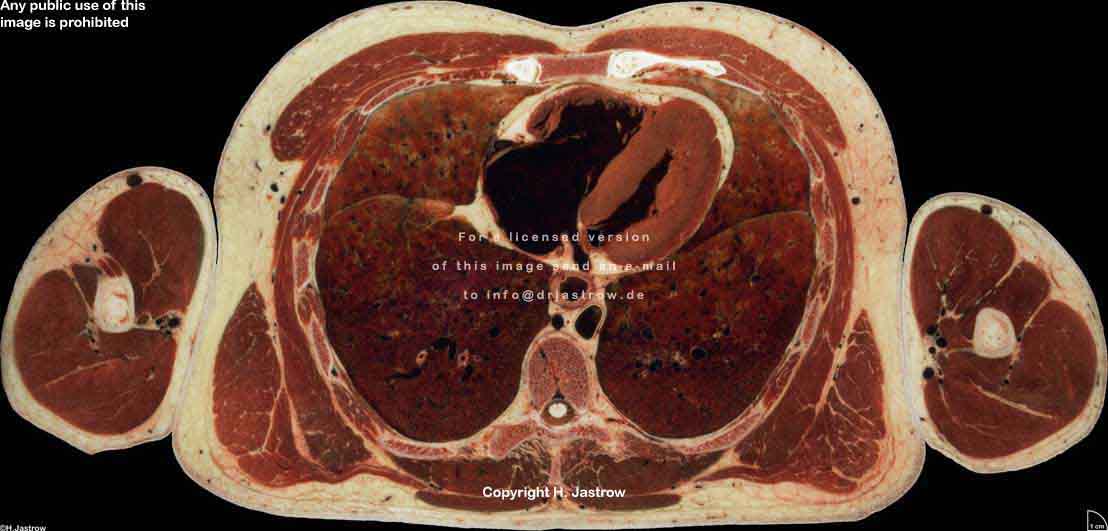

Visible Human male: Sectio transversalis 1453